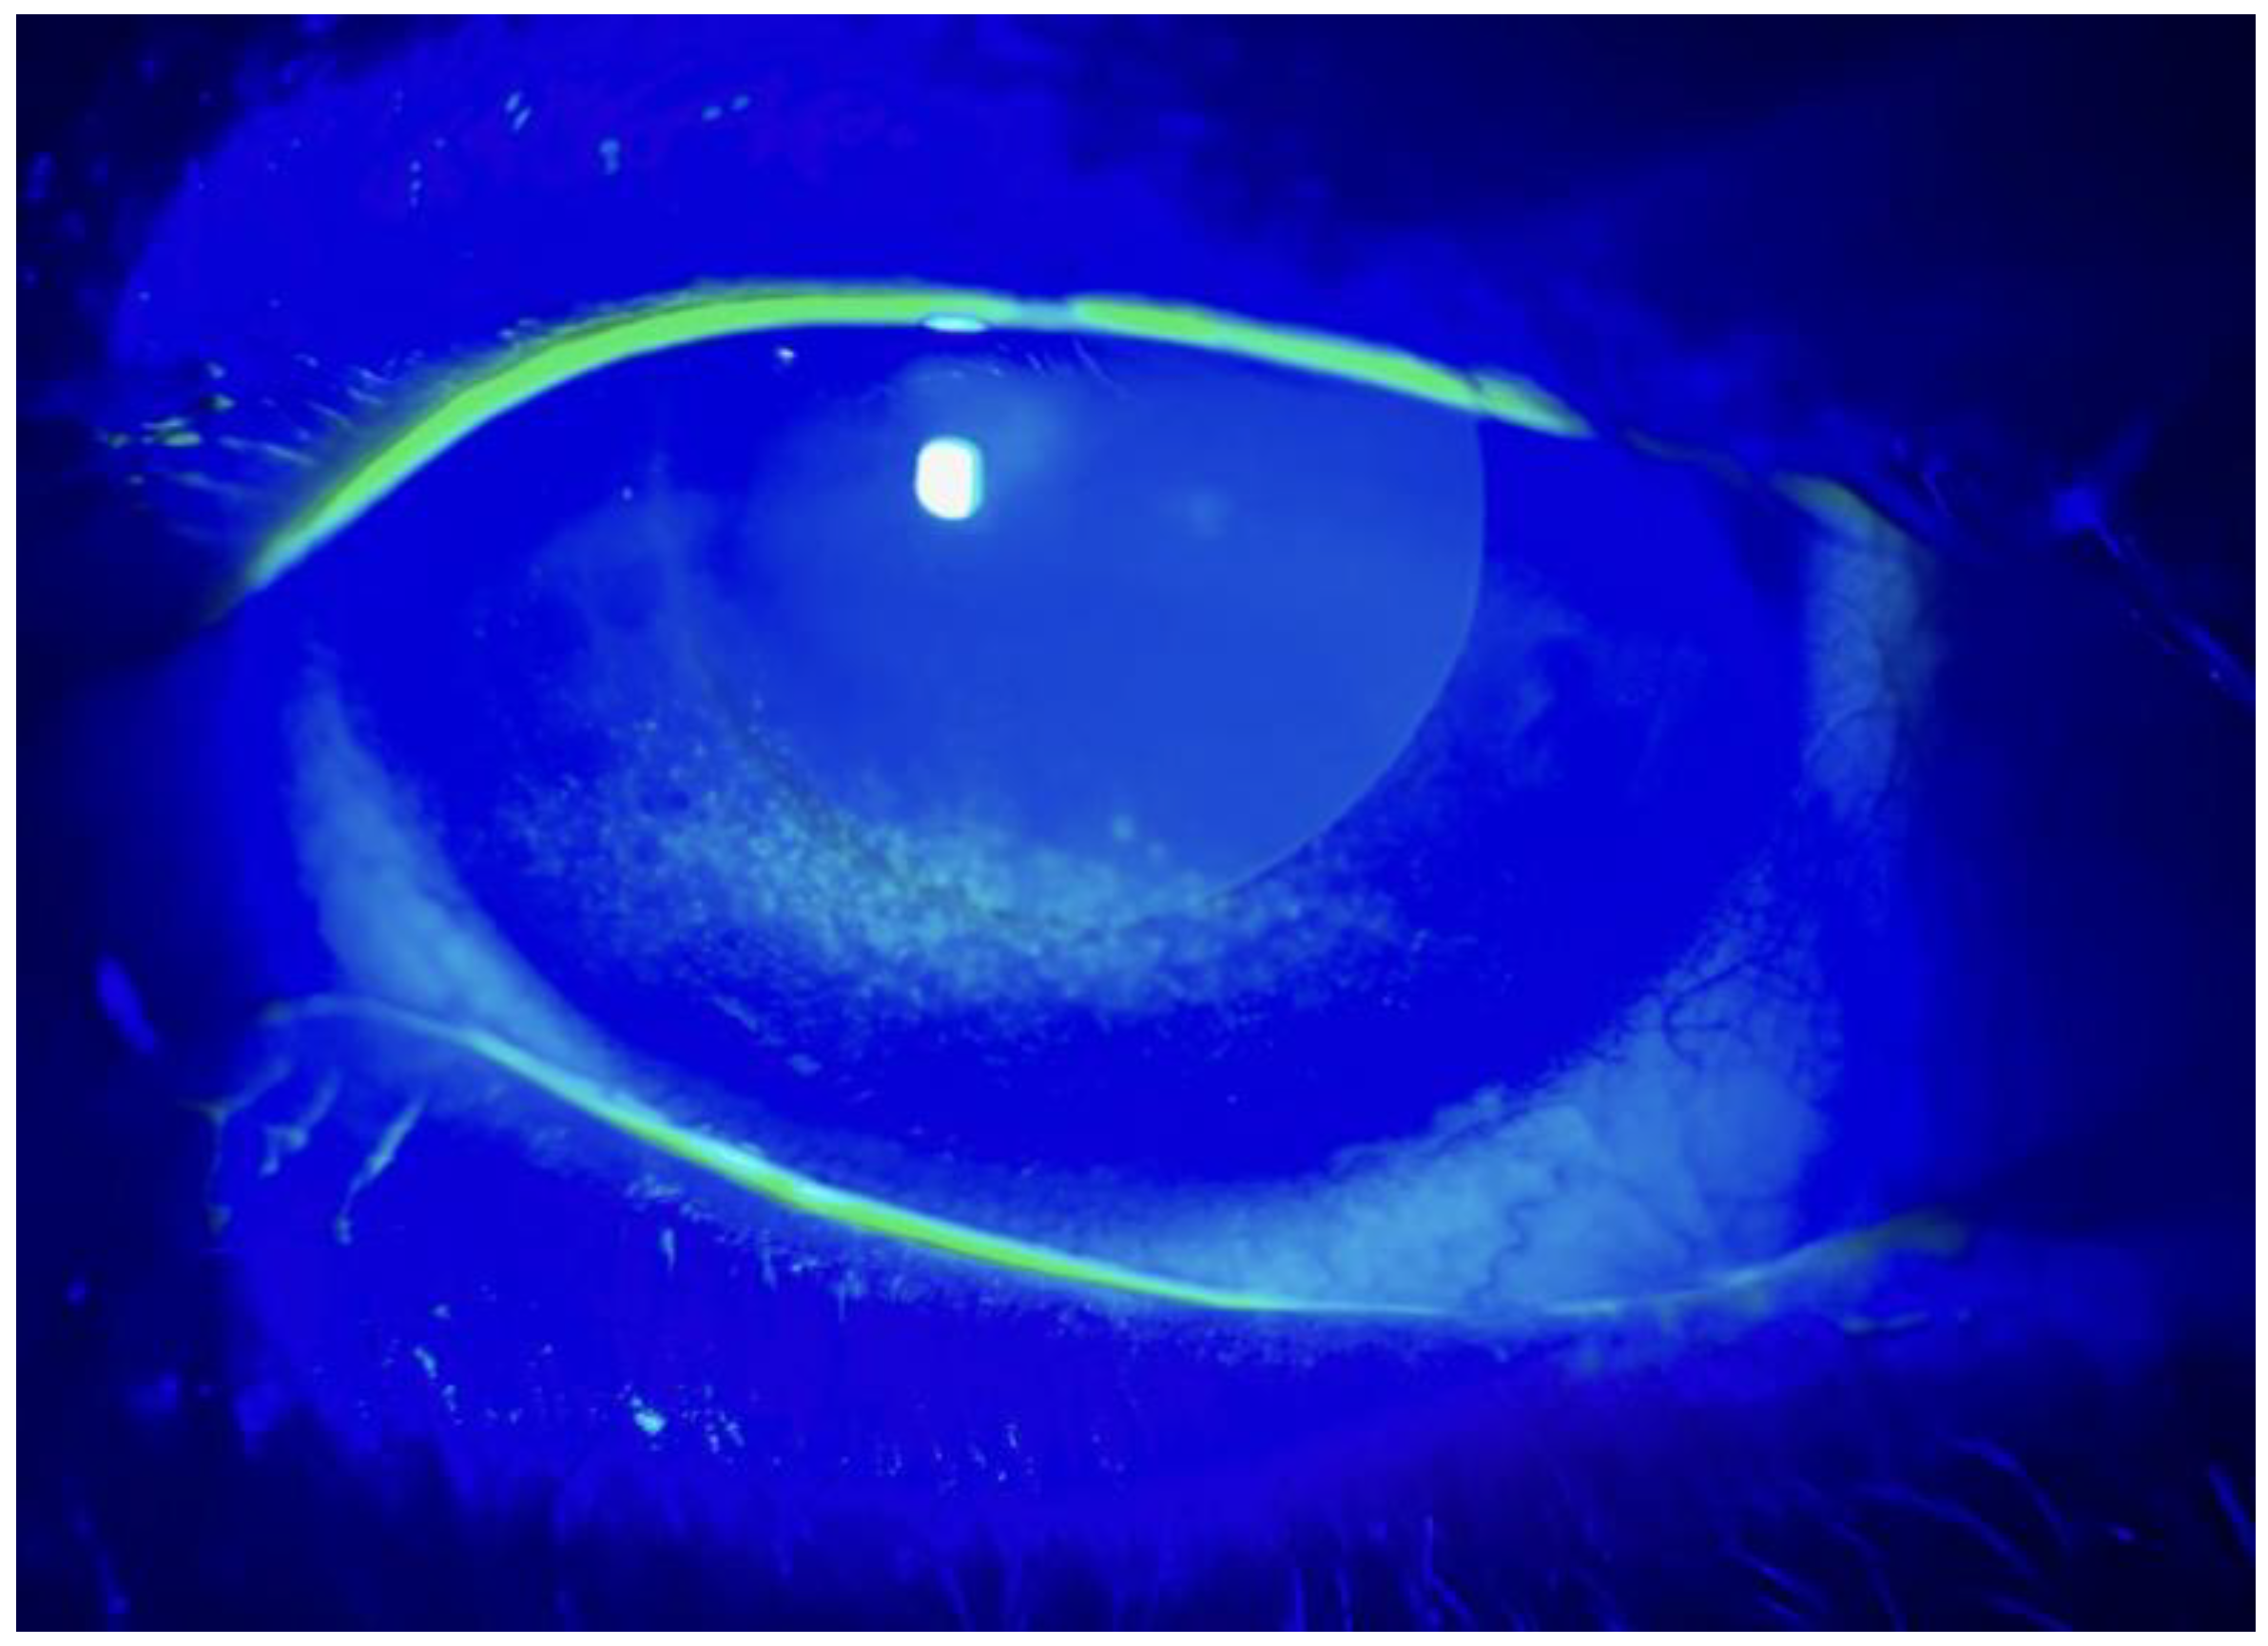

- The Non-Invasive Break-Up Time (NIBUT) and Break-Up Time (BUT);

- Fluorescein staining with digital photography and Oxford classification;